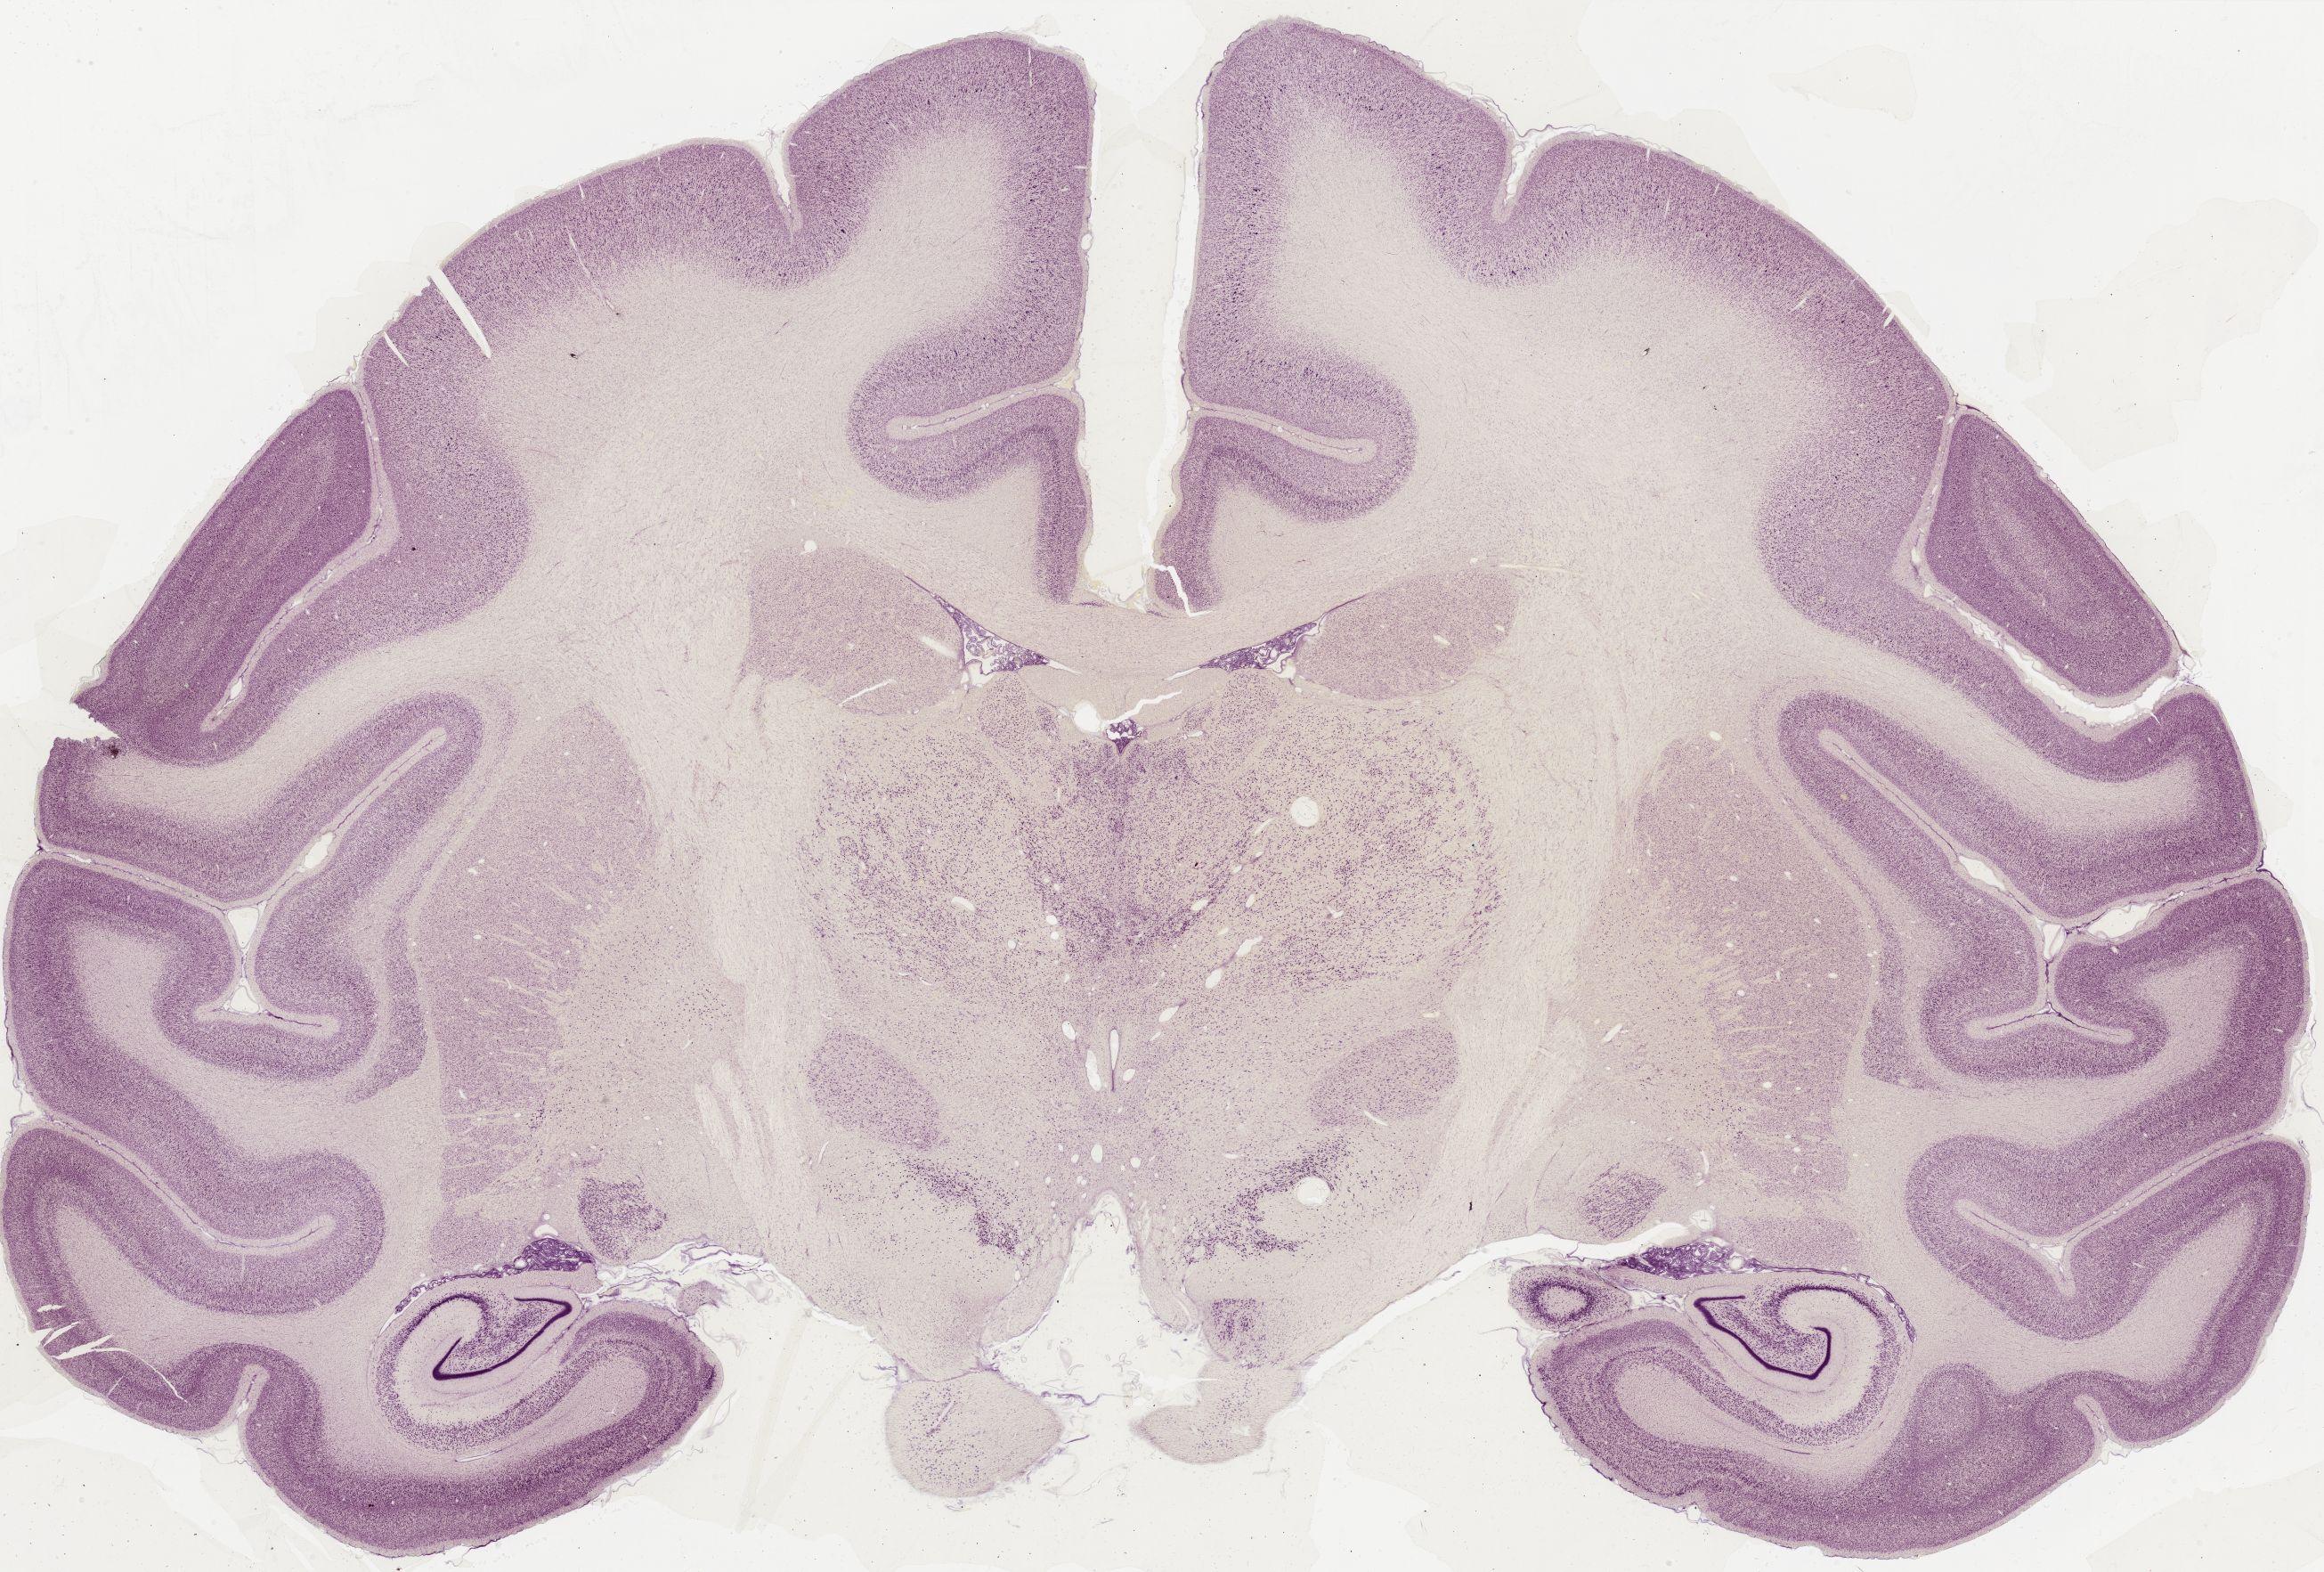

Datasets -> Macaca Mulatta -> Nissl, coronal, histo, Whole-Brain, adult [ Metadata ] · Source: Edward G. JonesDisplaying Sections 1 thru 40 of 56 Sections for this DatasetPages: 1 2 1339 - labeled 1301 - labeled 1251 - labeled 1201 - labeled 1151 - labeled 1102 - labeled 1051 - labeled 1040 - labeled 1020 - labeled 1006 - labeled 1001 - labeled 0982 - labeled 0975 - labeled 0958 - labeled 0951 - labeled 0941 - labeled 0924 - labeled 0920 - labeled 0901 - labeled 0894 - labeled 0878 - labeled 0875 - labeled 0859 - labeled 0851 - labeled 0845 - labeled 0824 - labeled 0823 - labeled 0801 - labeled 0800 - labeled 0785 - labeled 0781 - labeled 0771 - labeled 0770 - labeled 0732 - labeled 0721 - labeled 0720 - labeled 0701 - labeled 0682 - labeled 0680 - labeled 0666 - labeledPages: 1 2